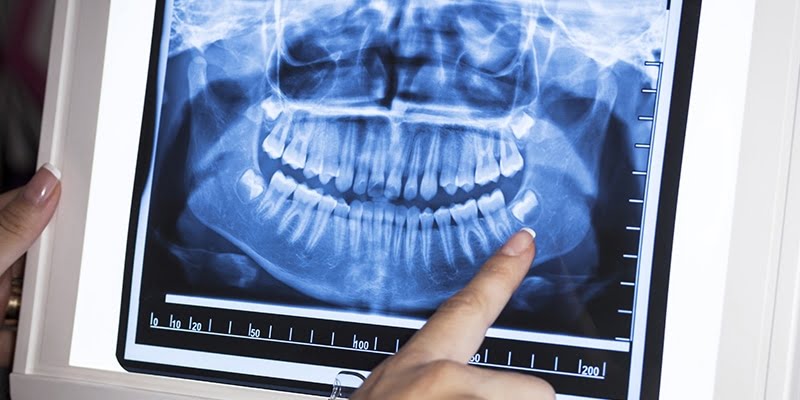

Below are some screen images of the information we gain that is invaluable to the dental Implant process as it allows to visualise the placement in 3D. The main benefit is that as we know the anatomy of the site where the implant is placed we do not have to make large cuts(incisions) in the gum. Implants are placed through a very small hole in the gum therefore reducing healing time and post surgery discomfort and swelling.